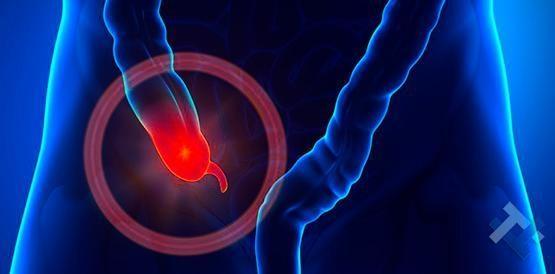

Ο Γενικός Χειρουργός Λιάγκος Γεώργιος MD PhD εκτελεί τις επεμβάσεις Λαπαροσκοπικά, Ενδοσκοπικά, Ανοιχτά Ελάχιστα Επεμβατικά και με Laser. Η θεραπεία εξατομικεύεται σε κάθε ασθενή ανάλογα με τις ανάγκες του. Αναλαμβάνει περιπτώσεις όπως κήλες και κοιλιοκήλες (αντιμετώπιση βουβωνοκήλης, αντιμετώπιση ομφαλοκήλης, θεραπεία επιγαστρικής κήλης, κήλη των αθλητών (Σύνδρομο κοιλιακών προσαγωγών), αντιμετώπιση μετεγχειρητικής κήλης, θεραπεία Μηροκήλης), πέτρες στη χοληδόχο κύστη, λαπαροσκοπική χολοκυστεκτομή, αντιμετώπιση Κύστη Κόκκυγος με λέιζερ (laser), παθήσεις πρωκτού, χειρουργική laser σύγχρονων κυκλικών ινών (αιμορροΐδες αντιμετώπιση, θεραπεία αιμορροϊδων με laser (LHP), αφαίρεση αιμορροΐδων με υπερήχους (HALL-RAR), χωρίς Χειρουργείο με ελαστικούς δακτυλίους (Τεχνική BARON-RBL), θεραπεία ραγάδας πρωκτού (Ραγάδα δακτυλίου), θεραπεία περιεδρικού συριγγίου, θεραπεία περιεδρικού αποστήματος, κονδυλώματα πρωκτού Θεραπεία, δερματικό ράκος (Skin tag) εκτομή, αντιμετώπιση Kνησμού, καρκίνος πρωκτού θεραπεία), παθήσεις Δέρματος, χειρουργική με laser CO2, αφαίρεση μορφωμάτων δέρματος - βιοψίες, αφαίρεση ελιάς (Σπίλου), σμηγματογόνος κύστης θεραπεία, αφαίρεση λιπώματος, είσφρυση όνυχος χειρουργείο, καρκίνος δέρματος θεραπεία, οξεία σκωληκοειδίτιδα, παθήσεις Λεπτού και Παχέος Εντέρου, ειλεός λεπτού εντέρου, εκκολπωμάτωση (Εκκολπωματίτιδα) σιγμοειδούς, καρκίνος παχέος εντέου, κολοστομίες, port χημειοθεραπείας κ.α. εξυπηρετώντας Παγκράτι και γύρω περιοχές.